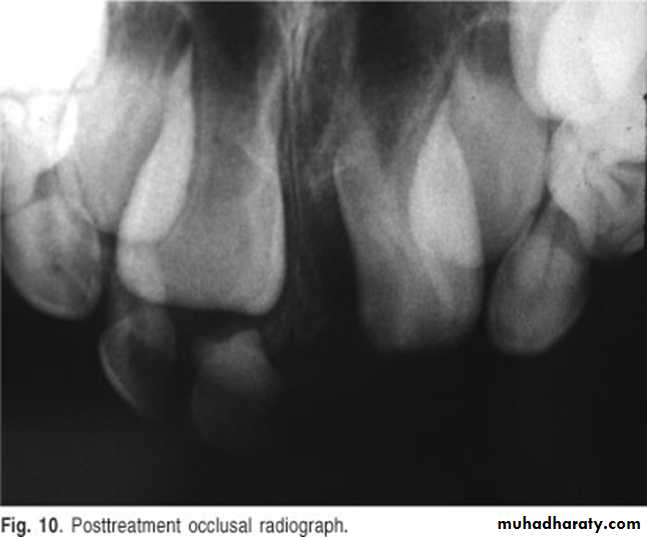

A 11-year-old female with swelling on the right side.

impacted canine